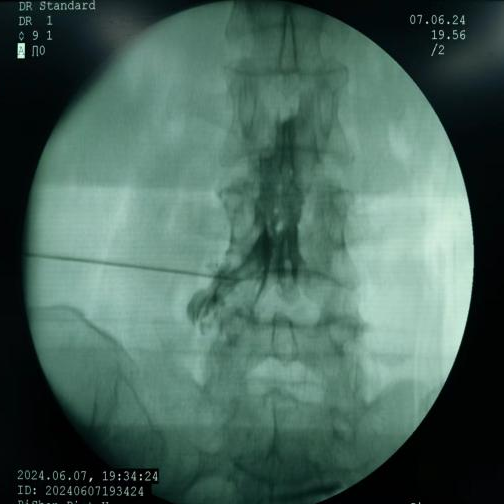

脊髓电刺激植入术:将电极植入脊柱附近硬膜外腔,通过电流刺激脊髓,阻断疼痛信号传至大脑,有效治疗慢性顽固性神经痛。

脊髓电刺激植入术